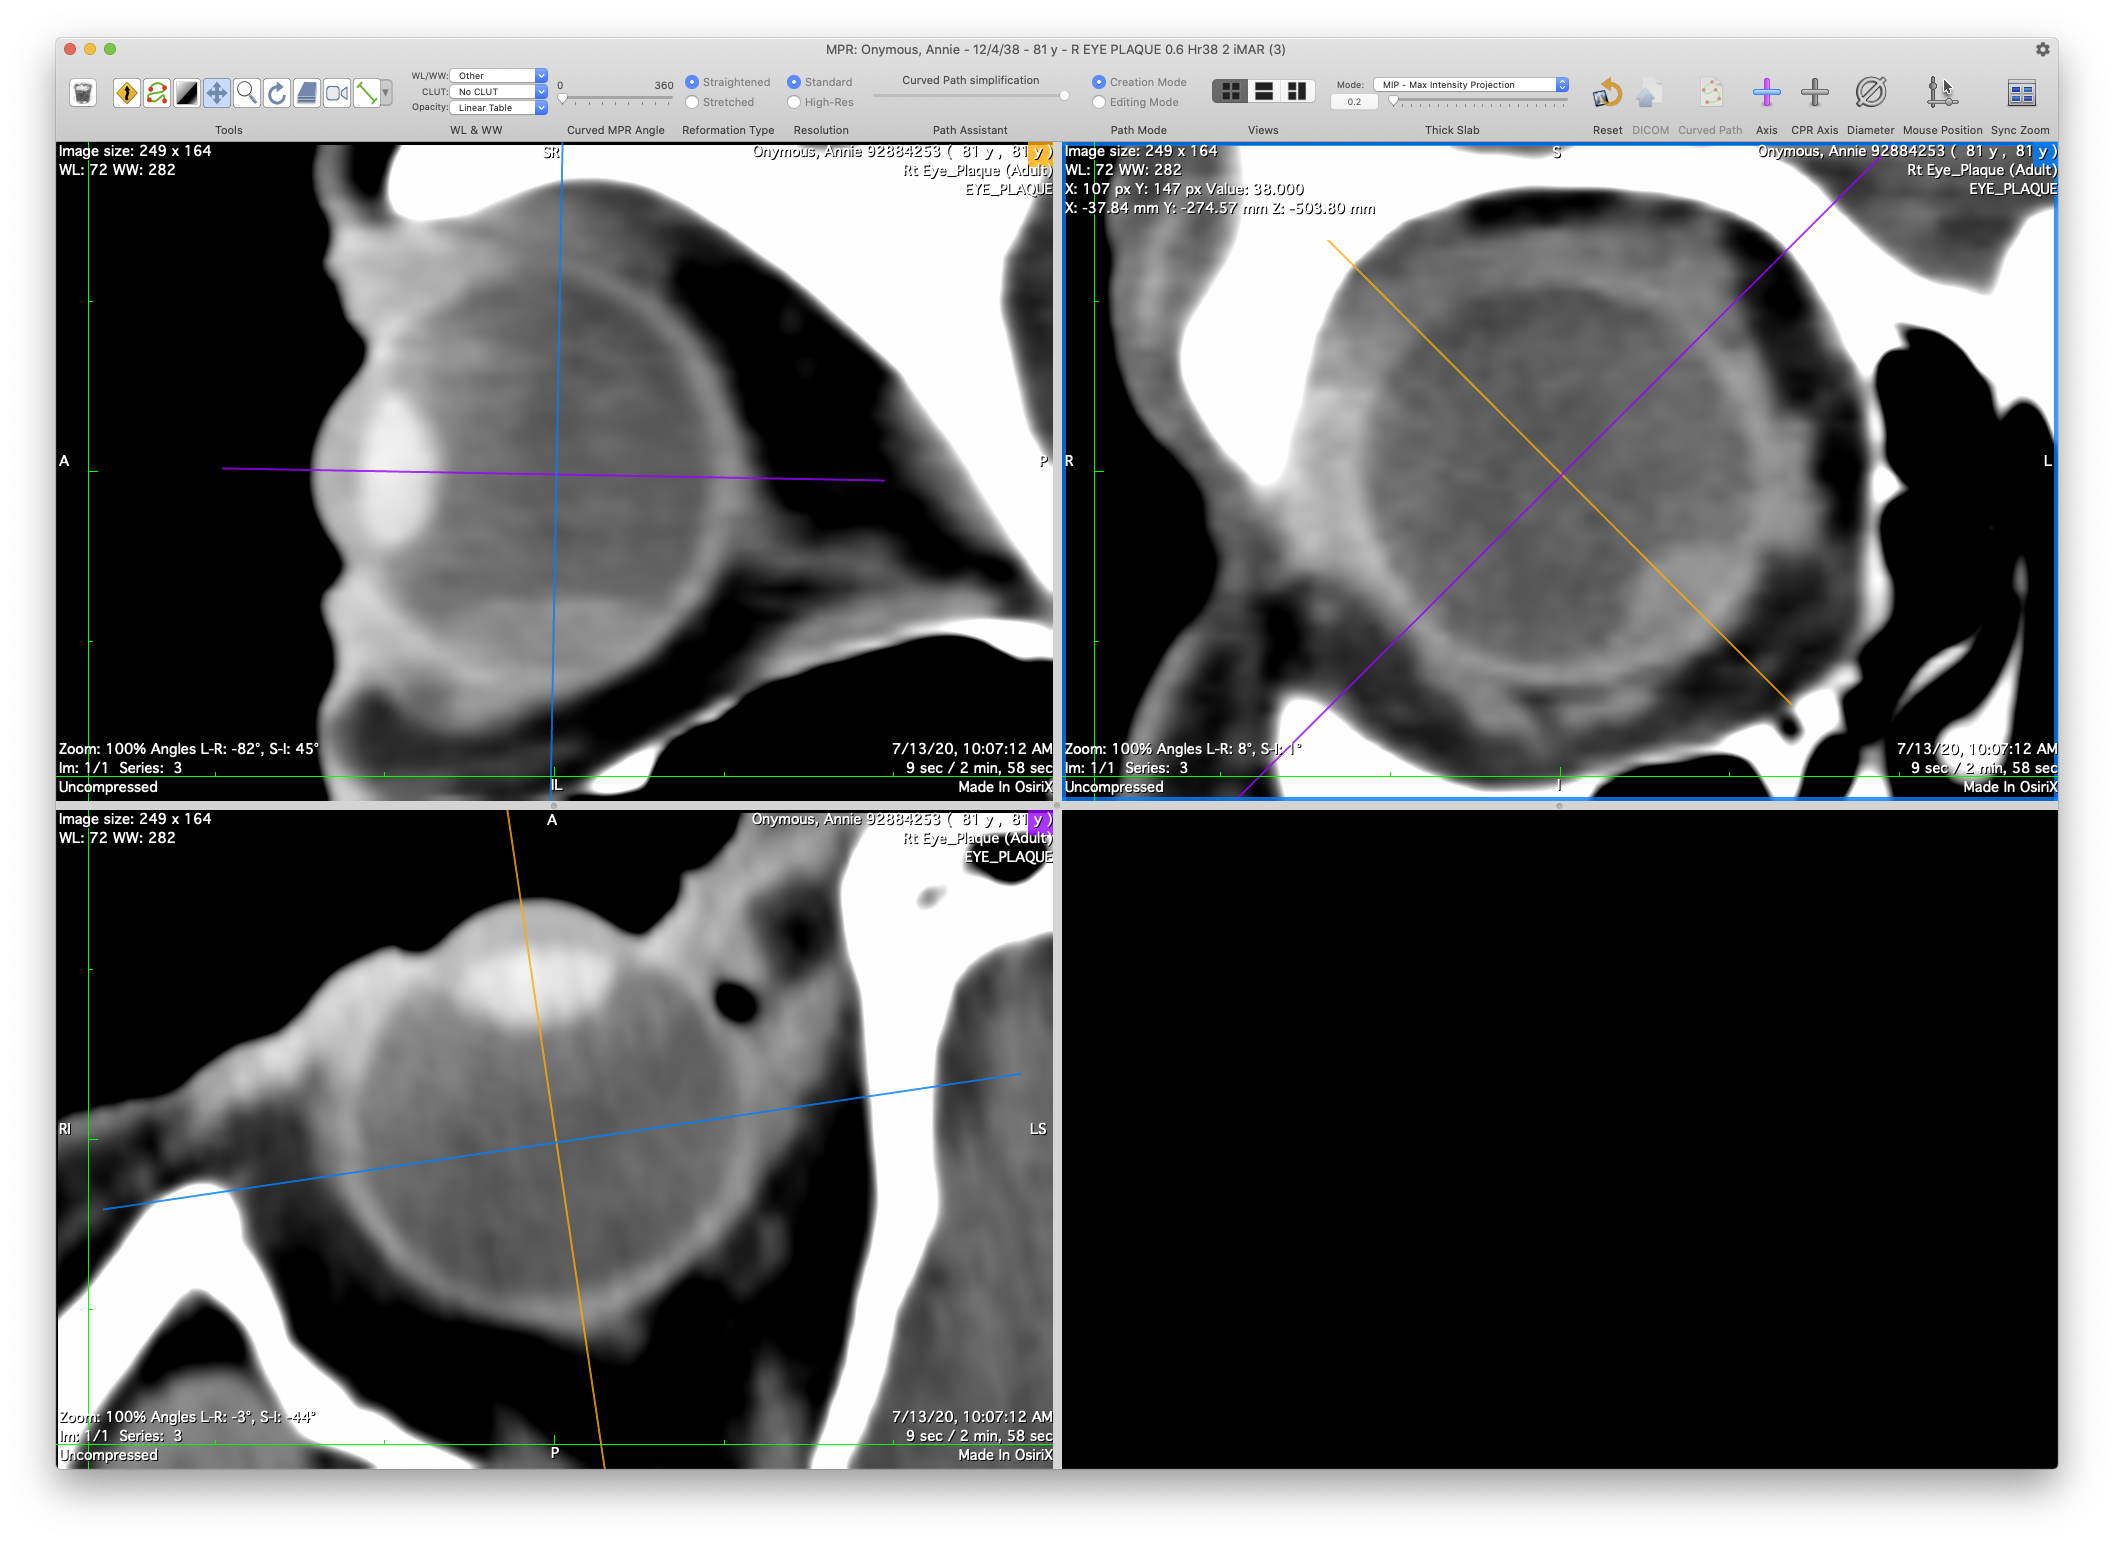

The 3D Curved-MPR 4-pane window

• SyncZoom.png In the window toolbar (upper right corner), be sure the Sync Zoom control is enabled. If the control is not visible, increase the window width until you can see control. Once enabled, you can resize the window as you like. When Sync Zoom is enabled, changes in one pane will be propagated to the other panes.

• Quadrant I: Coronal reconstruction in the upper-right pane.

• Quadrant II: Sagittal reconstruction in the upper-left pane.

• Quadrant III: Axial reconstruction in the lower-left pane.

• Quadrant IV: The lower-right pane is empty.

• Placing the cursor over the intersection of the axes crosshairs in any image will produce a cursor that translates the two axes in unison. Drag the crosshairs to the center of the affected eye.

• Placing the cursor over an axis away from the intersection will produce a rotation-cursor.

• Drag and rotate the axes such that the yellow-orange axis marks the left-right bisecting plane of the eye (ie the sagittal meridian, aka the 12 to 6 o'clock meridian on the retinal diagram), the blue axis marks the coronal plane with the largest diameter (ie the approximate equator of the eye), and the purple axis marks the bisecting (inf-sup) axial meridian plane of the eye through the optic disc (3 to 9 o'clock meridian on the retinal diagram).

• UPPER-RIGHT: In this coronal-equatorial pane, rotate the purple axis so that it bisects (inf.-sup.) BOTH eyes. Assuming contralateral symmetry of the orbits, this rotation will correct for the most commonly encountered rotation of the head in the scanner. This purple axis corresponds to the Y-axis of Plaque Simulator's 3D model of the eye. The yellow-orange axis corresponds to the Z-axis of Plaque Simulator's 3D model of the eye.

• LOWER-LEFT: In this axial image the yellow-orange axis corresponds to the X-axis of Plaque Simulator's 3D model of the eye. It passes through the apex of the cornea, the midpoint of the lens, and the posterior pole of the eye. The blue axis corresponds to the Y-axis of Plaque Simulator's 3D model, representing the transition from the posterior hemisphere to the anterior oblate spheroid elements of the 3D model.

• UPPER-LEFT: In this sagittal image the blue axis becomes Plaque Simulator's Z axis, also representing the transition from the posterior hemisphere to the anterior oblate spheroid elements of the 3D model. The purple axis is Plaque Simulator's X axis.

• Note: because the patient's eye may not have been looking "straight ahead" during the scan, the axial, equatorial and sagittal reconstructions of the eye as expected by Plaque Simulator might not be parallel to the axial, coronal and sagittal planes of the body or the CT scanner. It is important to provide Plaque Simulator reconstructions that correspond to the geometry expected by Plaque Simulators 3D model of the eye.